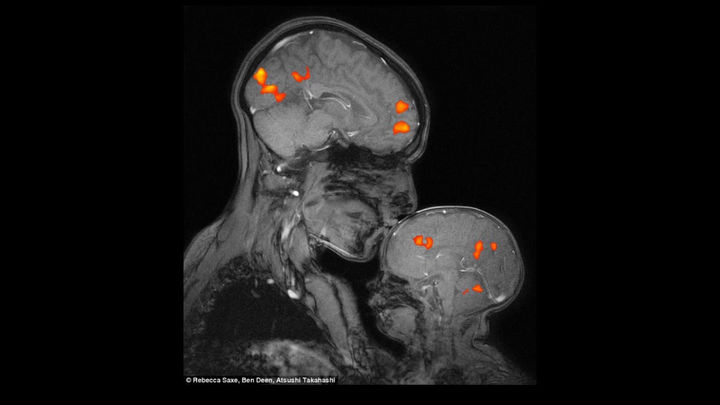

Bu suratda ikkita inson - ona va bola miyasining porlayotganini ko‘rish mumkin. Bu ikki asab tizimining sinxron raqsi, so‘zi yo‘q til, sevgi kodi...

Ona mehrining ilmiy suratini amalga oshirish maqsadida funksional magnit-rezonansli tomografiya o‘tkazildi.

Ona bolasini o‘pganda, u nafaqat uning terisiga, balki o‘z farzandining miyasiga tegib ketar ekan. Bu oddiygina tuyuladigan aloqa ona va bolani chuqur o‘zgartiradigan ko‘rinmas aloqalar bo‘ronini qo‘zg‘atib yuboradi.

Shu lahzada onada:

• miya yadrosiga yondosh zavqlanish, rag‘bat va motivatsiya funksiyalari uchun mas’ul bo‘lgan hududlar tizimi - dofamin markazlari  faollashadi;

• emotsional jarayonlarni tartibga solishda asosiy rol o‘ynaydigan miyadagi bodomsimon tizim (mindalina) ishga tushadi, tananing ko‘plab hayotiy funksiyalari boshqarilishining asosiy markazi gipotalamus kuchli hissiy, himoya reaksiyalarni keltirib chiqaradi.

• stressni kamaytiradigan, aloqani mustahkamlaydigan va deyarli buzilmaydigan birikma hosil qiluvchi sevgi gormoni oksitotsin ajralib chiqadi.

Bolada:

• yurak tinchlanadi, tana bo‘shashadi;

• stress gormonlari darajasi pasayadi;

• u o‘zini xavfsiz, muhabbat og‘ushida his qiladi;

• aynan shu daqiqada miya farzandning kelajakdagi butun hayotiga, ishonch, yaqinlik va sevish qobiliyatiga ta’sir ko‘rsatadigan muhabbatni qayd qila boshlaydi.

Qo‘shimcha ravishda ona miyasi xuddi eng qimmatli narsani himoya qilayotgandek ishlay boshlaydi.

Bolaning miyasi esa bu signalni xotirjam qabul qiladi.

Ikkalasi ham almashinadi. So‘zsiz. Faqat o‘zaro bog‘liqlikdan, iliqlikdan.

Bu sevgi neyrobiologiyasi. Bu bizning ich-ichimizda iz qoldiradigan g‘amxo‘rlikdir. Va bularning barchasi - bitta, oddiy, samimiy bo‘sa tufayli sodir bo‘ladigan holatlar.